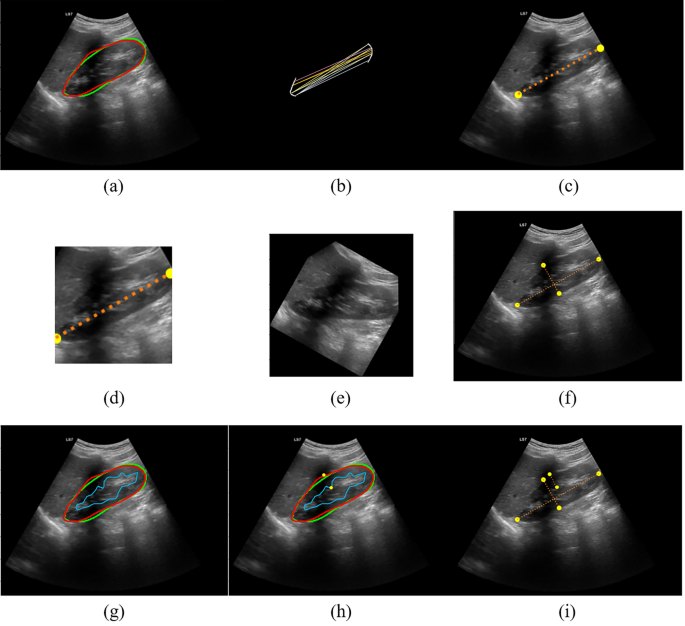

After kidney segmentation in sagittal and axial views, post-processing algorithms were performed to calculate the renal dimensions and volume. These algorithms, grouped based on the input image and illustrated in Fig. 2, are presented in the following:

Post-processing of sagittal view image. (a) Segmentation of the capsule. The ground truth is the green contour and the predicted mask is the red one. (b) Finding the farthest pairs of points between two poles, (c) kidney length (KL), (d) tailored crop, (e) rotation of the image to make it horizontal, (f) finding kidney thickness, (g) segmentation of sinus, (h) finding the farthest pairs of points between sinus and capsule’s masks, and (i) parenchyma length.

Post-processing of sagittal images

The segmented area of the sagittal-view images was used to calculate the kidney length (KL), thickness (KT), and parenchymal thickness. Figure 2a–e represents the post-processing related to the calculation of KL. Figure 2a shows the segmented kidney capsule in the sagittal view image. The green contour represents the ground truth, delineated by the expert radiologist, and the red contour represents the predicted contour by Fast-Unet++. The upper and lower poles of the kidney, which were extracted from the mask, are shown in Fig. 2b. The farthest pairs of points between the two poles were found using a grid search algorithm. The colored lines in Fig. 2b illustrate the procedure, and the determined points are shown in Fig. 2c. The KL is the distance between these two points.

The second row of Fig. 2 is related to the calculation of the kidney thickness. First, the image was cropped using a tailored-crop algorithm based on two points annotating the KL48. The resulting square-shaped image enclosed the kidney and some of the background, as shown in Fig. 2d. Next, the cropped image was rotated-padded based on the angle achieved from the KL’s line. In this way, the kidney would be horizontal (Fig. 2e). Finally, to achieve the kidney thickness, the topmost point of the rotated mask was found, and the corresponding downmost point was reached. These points annotate the kidney thickness depicted in Fig. 2f.

The algorithm of the parenchymal thickness calculation is shown in the third row of Fig. 2. The kidney sinus was segmented using Fast-Unet++, and the farthest points between the upper contour of the kidney mask and the sinus mask were found (Fig. 2g, h). The distance between these two points is considered the parenchymal thickness.